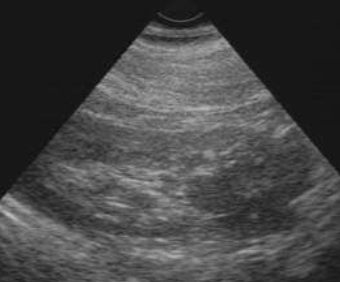

| Рис. 6.2. Сонограмма мочевого пузыря и предстательной железы (сагиттальная плоскость). Мочевой пузырь− норма. Предстательная железа увеличена, структура ее неоднородная – доброкачественная гиперплазия предстательной железы. |